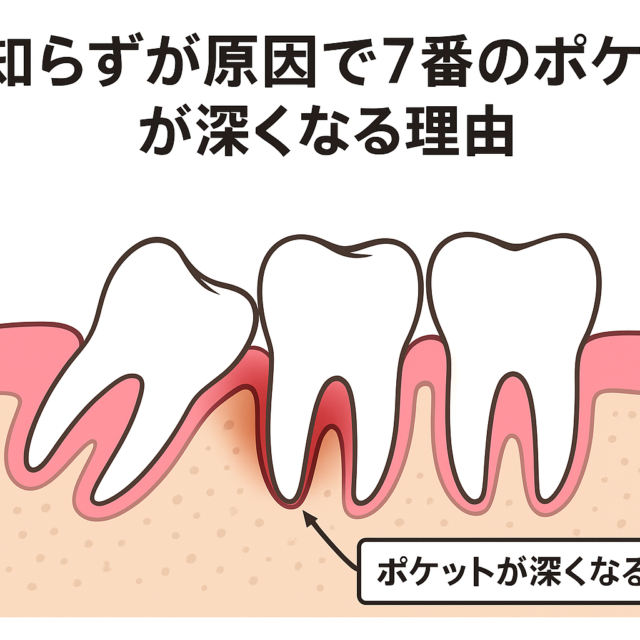

お口の中の状態としては、上下噛み合わせたときに前歯が当たっていない(開咬)=不正咬合です。

この不正咬合をそのままにしておくと、

- 食べ物がよく噛めない

- むし歯になりやすい

- 歯周病になりやすい

- 口が閉じにくい為、口腔乾燥により口臭の原因になる

- アゴの関節に負担をかける(顎関節症)

- 歯が割れたり折れたりしやすい

などの問題がでてきます。